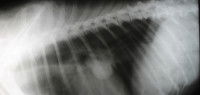

Une échographie et/ou un scanner sont parfois réalisés ensuite afin d’évaluer le stade de la maladie et l’éventuelle extension à d’autres organes et parties du corps.